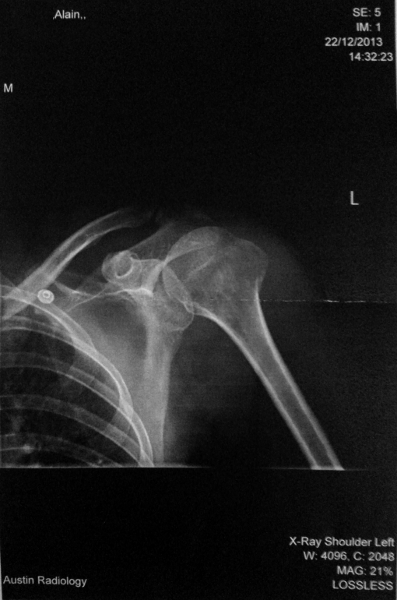

After a couple of hours of poking, prodding, X-raying, bandaging and waiting, I got the news. We were beginning to think it might just be bruising, but the fact that I still couldn’t move my arm after several hours didn’t bode well. In addition to a body covered in abrasions – left arm, right elbow, left thigh, left knee, right shoulder, right hip – I had sustained a fracture. But as fractures go, I was lucky: an undisplaced fracture of the greater tubercle.

There is a fracture in here somewhere. That sentence is a good sign. Not quite up there with better known x-rays (thankfully).

With this type of fracture, pain is the indicator of progress, and exercise is generally good, with bone healing responding to stress.